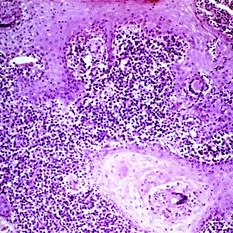

Slide 5-7 Slide 5-7Feb 20 2019 by Lancaster Course in Ophthalmology Discrete pink clumps of epithelioid cells in sarcoid. Note the giant cell in one clump. Condition/keywords: epithelioid cells, giant cell, sarcoid

Slide 5-8 Slide 5-8Feb 20 2019 by Lancaster Course in Ophthalmology Small chalazion in situ in the lid. Lipogranulomatous reaction around large and small clear spaces (pools of dissolved fat) from a single obstructed meibomian lobule. Condition/keywords: chalazion, lipogranulomatous reaction, meibomian lobule, situ